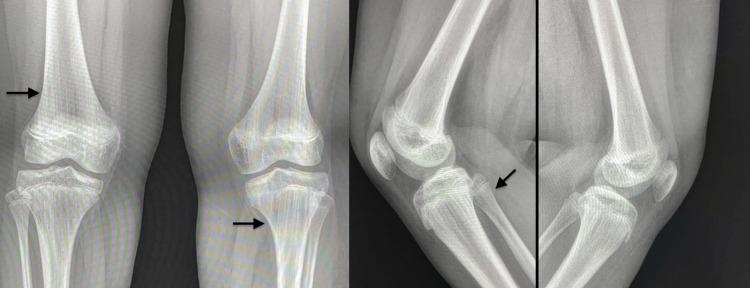

Focal dermal hypoplasia (FDH), also known as Goltz syndrome, is a rare syndrome described in the literature. Patchy skin hypoplasia is the most evident sign. Hyperpigmentation, hypopigmentation, papillomas, limb defects, and orofacial manifestations have also been reported. A 12-year-old Saudi girl with unremarkable family history presented with FDH. The diagnosis was confirmed using a genetic study. Physical examination revealed asymmetrical streaks of vermiculate dermal atrophy, telangiectasia with hyperpigmentation, and hypopigmentation on the left half of the face, trunk, and bilateral extremities. It appears along Blashko lines. No mental impairment was observed. Intraoral examination generalized plaque-induced gingivitis with erythematous gingival hyperplasia. Examination of the teeth showed generalized enamel hypoplasia with abnormal tooth formations, malalignment, microdontia, spacing and tilting, and minimal caries. As reported cases of FDH are rare worldwide, this syndrome is yet to be fully understood. As the manifestation of the syndrome varies among cases, the management of each case is unique. This emphasizes the importance of reporting cases of FDH.

局灶性真皮发育不全(FDH),也称为戈尔茨综合征,是文献中描述的一种罕见综合征。片状皮肤发育不全是最明显的体征。也有报道称存在色素沉着过度、色素减退、乳头状瘤、肢体缺陷和口面部表现。一名12岁的沙特女孩,家族史无异常,患有局灶性真皮发育不全。通过基因研究确诊。体格检查发现左侧面部、躯干和双侧肢体有不对称的蠕虫状皮肤萎缩条纹、伴有色素沉着过度的毛细血管扩张和色素减退,沿布拉斯科线分布。未观察到智力障碍。口腔检查发现广泛性菌斑性牙龈炎伴牙龈红斑增生。牙齿检查显示广泛性釉质发育不全,伴有牙齿形态异常、排列不齐、过小牙、牙间隙和牙倾斜,以及轻度龋齿。由于全球范围内报道的局灶性真皮发育不全病例很少,该综合征尚未被完全了解。由于该综合征在不同病例中的表现各异,每个病例的治疗都是独特的。这强调了报告局灶性真皮发育不全病例的重要性。